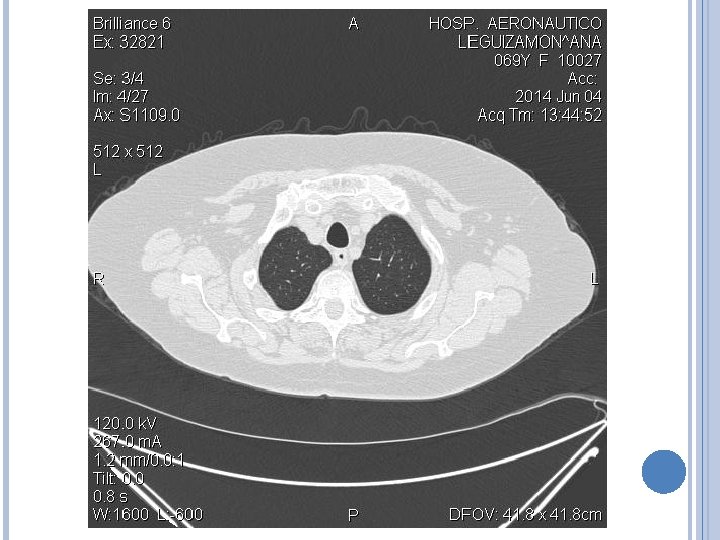

IMAGENES